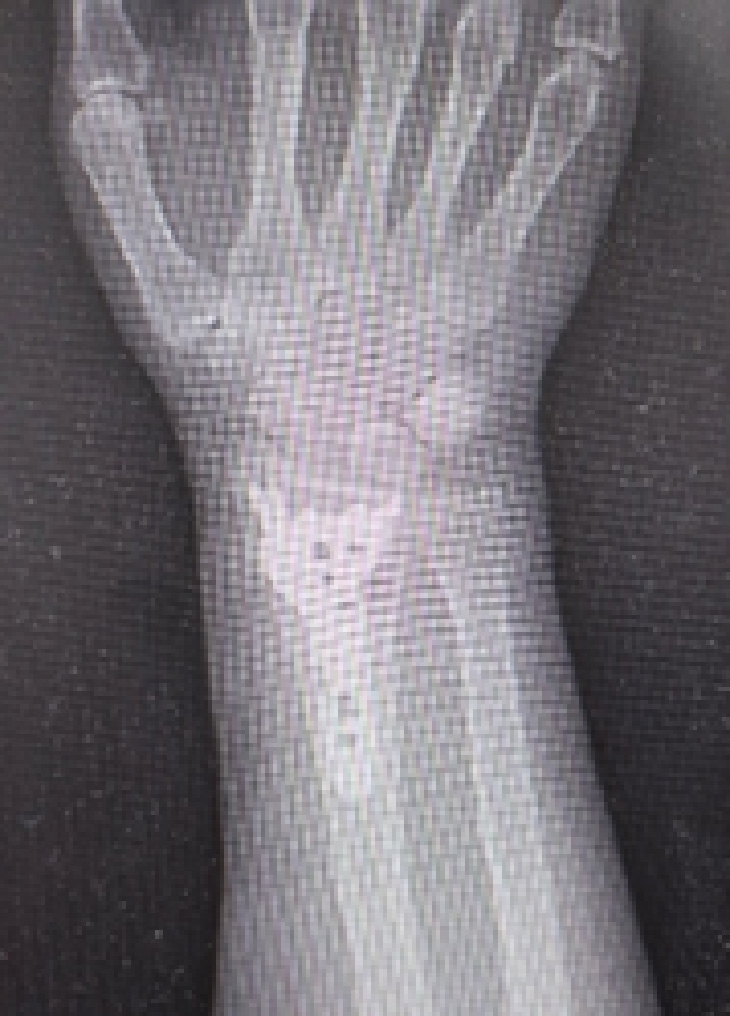

橈骨遠位端骨折

骨を治すだけでなく、“動きを取り戻す”治療

橈骨遠位端骨折とは

橈骨遠位端骨折は、手首の骨(橈骨)の先端部分が折れる骨折です。

転倒して手をついたときに多く発生し、特に中高年の女性や骨粗しょう症のある方に多く見られます。

見た目は軽い捻挫のようでも、実際には骨折していることがあり、適切な治療を行わないと手首の変形や可動域の制限が残る場合があります。

早期の診断と治療が大切です。